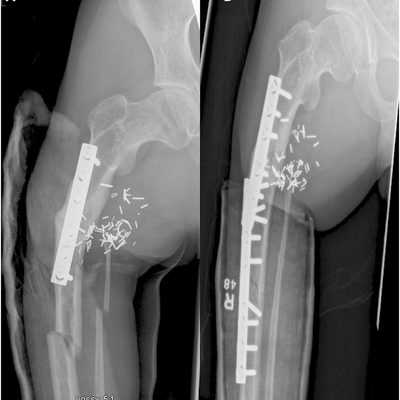

Click on an image below to view more info.